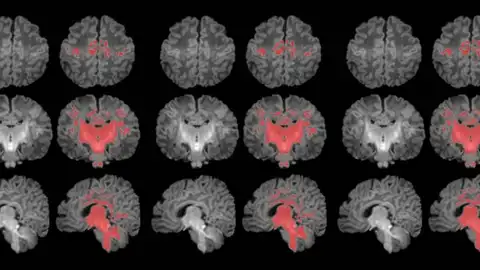

La exposición prenatal a la contaminación del aire se relaciona con una maduración más lenta del cerebro durante el primer mes de vida. Así lo ha revelado el primer estudio que mide con resonancia magnética la mielinización cerebral de los recién nacidos.

La mielinización es un proceso clave en la maduración del cerebro, en que la mielina recubre las conexiones neuronales y las hace eficientes para la transmisión de información. Los recién nacidos de madres expuestas a niveles más altos de partículas finas en suspensión durante el embarazo muestran una mielinización más lenta en esta etapa tan precoz de la vida.

Los resultados muestran una correlación clara entre una mayor exposición materna a PM2.5 durante el embarazo y una menor mielinización en el cerebro de los recién nacidos.